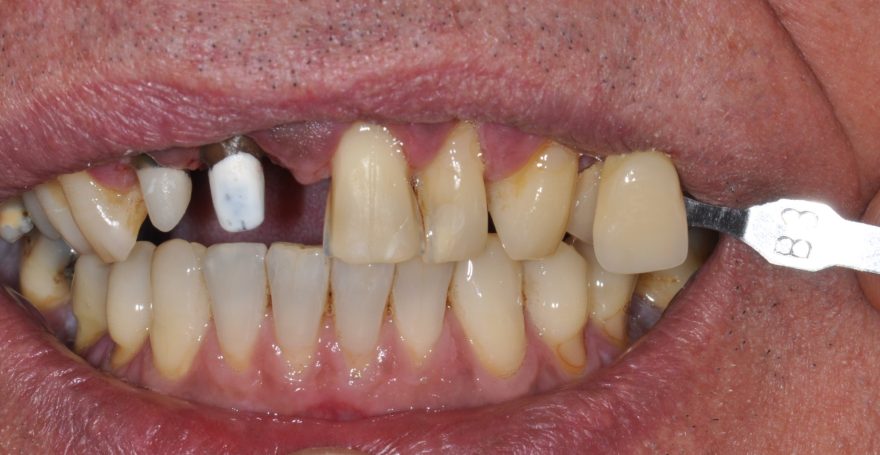

Veneerversorgung mit non-invasiven Veneers zur Verbesserung der Ästhetik.

Veneers und Krone zur Verbesserung der Ästhetik.

Frontzahnkronen Oberkiefer neu zur Verbesserung der Ästhetik.